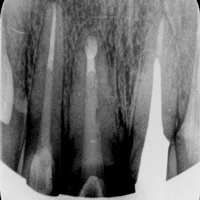

Pacjent z bólem, nieudana próba udrożnienia kanałów pod mikroskopem. Decyzja o resekcji korzenia policzkowego dalszego. RTG kontrolne rok po zabiegu.